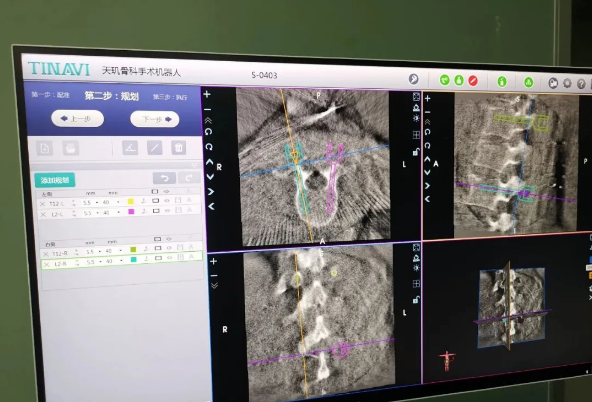

近日,天玑®骨科手术机器人落户南昌市第一医院,助力骨盆骨折闭合复位内固定术顺利完成。作为江西省首先采用5G引导下的骨科机器人手术,天玑®骨科手术机器人用它的“透视眼”,以三维影像扫描进行深层三维空间精准定位,为患者“量身定做”了最理想、最安全的教科书般通道,完成了复杂骨盆骨折微创治疗一次性完美置钉及腰椎骨折微创经皮置钉的首秀,成为江西省骨科发展的标志性事件,同时也是江西省骨科步入新型数字智慧骨科时代的重要里程碑事件。

天玑®骨科手术机器人系统由机械臂主机、光学跟踪系统、主控台车构成,“透视眼”、“稳定手”是它的厉害之处,因此一举解决了骨科手术有三大难题:视野差、精准难、不稳定。

➀ 光学跟踪系统就像是天玑®骨科手术机器人的“透视眼”,不仅透视洞察着肌肉骨骼的每一个深处,还实时监控每一个手术环节;

➁ 机械臂就是天玑®骨科手术机器人的“稳定手”,运动灵活、操作稳定,能达到亚毫米的精度;

➂ 主控电脑系统就等于天玑®骨科手术机器人的大脑,智能传达着医生的想法给以上两个设备,帮助医生进行“路径规划”,术中还能跟踪患者术中的移动,机器人手臂位置自动补偿,保障手术路径与计划路径一致。